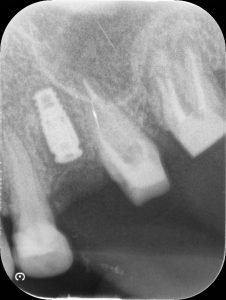

1件目のオペの様子です。

途中でレントゲンを撮って方向などをしっかり確認しながら進めて行きます。

最後にもう一度確認します。しっかりと埋入されております。